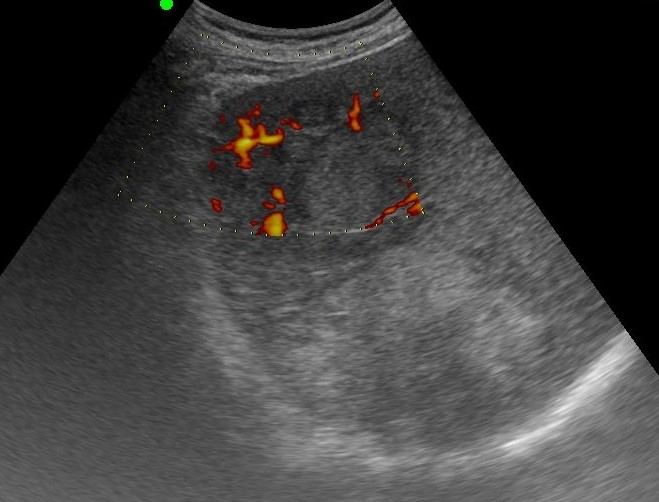

LIVER ) META |

2019.05.11 мЎ°нҡҢмҲҳ: 199 |